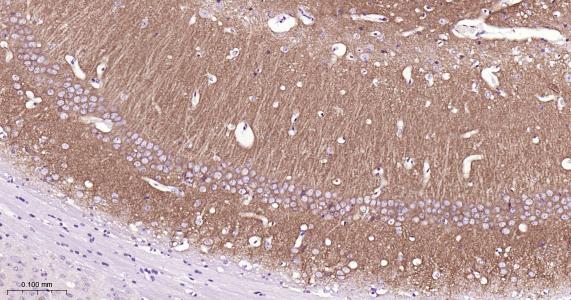

Paraformaldehyde-fixed, paraffin embedded Rat Cerebellum; Antigen retrieval by boiling in sodium citrate buffer (pH6.0) for 15 min; Antibody incubation with GluR1 Monoclonal Antibody, Unconjugated(bsm-62123R) at 1:200 overnight at 4°C, followed by conjugation to the bs-0295G-HRP and DAB (C-0010) staining.